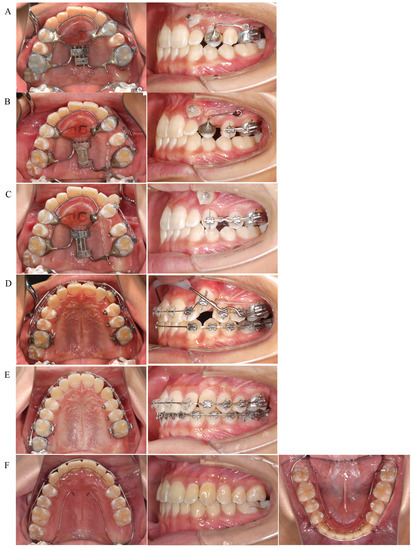

After extraction of the maxillary left second molar, a Hyrax-type expander was applied to the maxillary arch for distal movement of the maxillary left first molar. The patient was instructed to turn the screw a quarter-turn every 3 days. In parallel with the distal movement of the left first molar, traction of the left canine in the distal-buccal direction was initiated (Figure 6A). After about 3 months, when the patient had turned the screw a total of 32 times and an 8 mm expansion had been achieved, the occlusal relationship of the left molar was Angle Class I, indicating that the left first molar could be moved distally to the target position. The expansion screw was then fixed with resin to prevent relapse. A sectional archwire was placed on the left second premolar and first molar to initiate distal movement of the left second premolar (Figure 6B). Distal movement of the left second premolar was completed in 3 months. The left second premolar and first molar were sequentially ligated to prevent relapse of the second premolar. Then, the band on the left first premolar was removed, and a sectional wire was placed from the left first premolar to the first molar to initiate distal movement of the left first premolar (Figure 6C). After about 10 months, when the distal movement of the left first premolar was completed, the Hyrax-type expander was removed and an archwire was engaged in the left canine bracket to initiate leveling. In addition, to prevent the distally moved first molar from moving mesially, a lip bumper was applied to the first molars for reinforced anchorage during leveling (Figure 6D). After about 8 months, leveling of the canines was completed and detailing was initiated (Figure 6E). Three years and one month after the start of active treatment, detailing was completed and active treatment was terminated. Fixed retainers were placed between the maxillary and mandibular canines and on the mandibular left first and second molars, along with wraparound retainers, until the eruption of the maxillary left third molar. The maxillary wraparound retainer was designed to provide space for the eruption of the left third molar. The mandibular wraparound retainer was designed with a rest at the mandibular left second molar to prevent extrusion of the mandibular left second molar until the maxillary left third molar occluded with the opposing tooth (Figure 6F). Three years and six months after active treatment was terminated, the maxillary left third molar had fully erupted and occluded with the mandibular left second molar. We also encouraged the patient to have the mandibular left third molars extracted, because of no occlusal contact due to a reduced number of teeth in upper left segment. In addition, the maxillary and mandibular right third molars are impacted and scheduled for extraction.

Figure 6. Treatment progress. (A) Orthodontic occlusal guidance appliance applied. Distal movement of the maxillary left first molar started. Traction of the maxillary left canine started. (B) Distal movement of the maxillary left first molar completed. A sectional archwire was placed on the maxillary left second premolar and first molar to start distal movement of the left second premolar. (C) Distal movement of the maxillary left second premolar completed. A sectional archwire was placed from the maxillary left first premolar to the first molar to start distal movement of the left first premolar. (D) Distal movement of the maxillary left first premolar completed. Leveling of the maxillary left canine started. A lip bumper was applied to the maxillary first molars reinforced anchorage. (E) Leveling completed. Detailing started. (F) Active treatment was terminated. Fixed retainers were placed between the maxillary and mandibular canines and on the mandibular left first and second molars. Maxillary and mandibular wraparound retainers were applied.